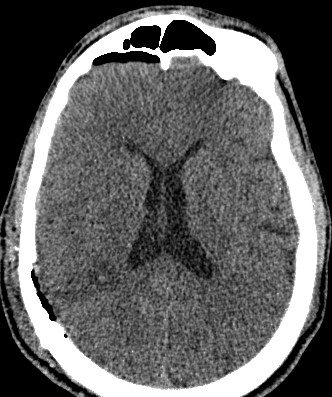

- Результат. В результате описанного метода было достигнуто радикальное и безопасное удаление каверномы, прилежащей к функционально значимой области головного мозга. В послеоперационном периоде отрицательной динамики в неврологическом статусе не отмечено. При контрольных КТ и МРТ головного мозга подтверждено радикальное удаление кавернозной мальформации. В удовлетворительном состоянии пациент выписан из стационара, вернулся к учебе в ВВУЗе.

Контрольные КТ и МРТ — состояние после удаления каверномы теменной доли без признаков осложнений.